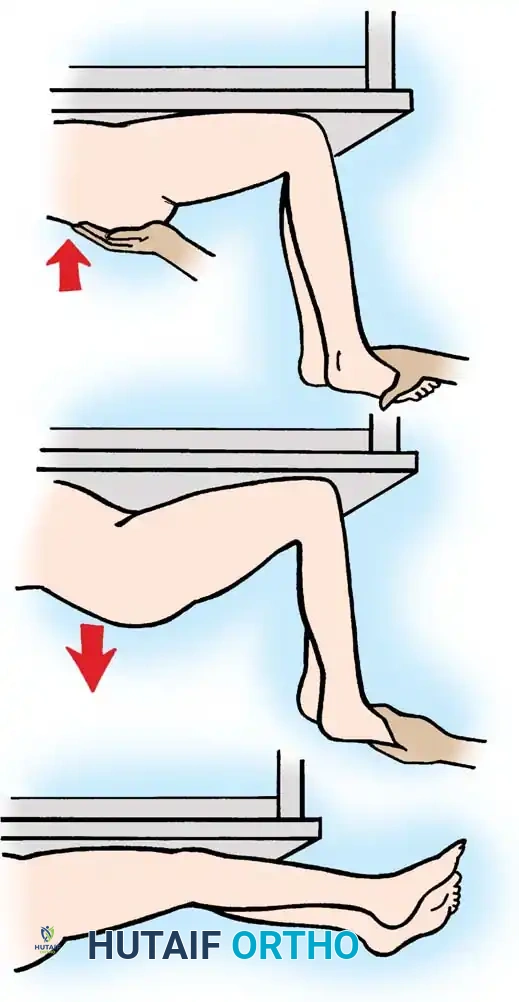

Quadriceps strength is best assessed with the patient supine and the lower legs dangling off the end of the examination table. The examiner extends the hips, allows the knees to flex passively, and then instructs the patient to voluntarily extend the knees against manual resistance.

Fig. 30-23 Testing for quadriceps strength. A, With hips extended, knees are allowed to flex off end of table. B, Patient voluntarily extends knees from flexed position against resistance.